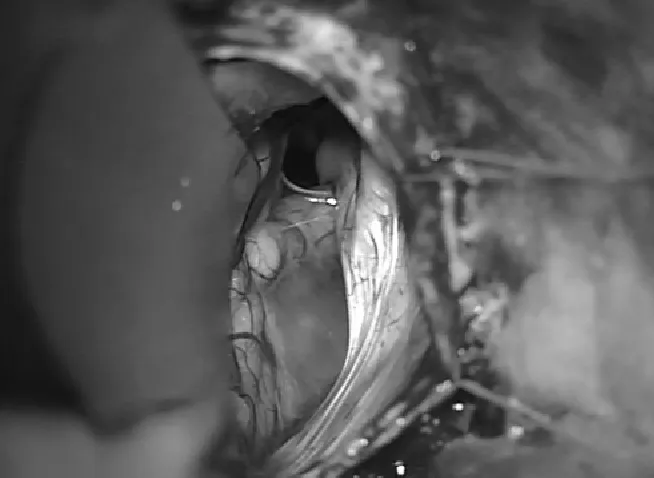

在温和的回缩后,蛛网膜囊肿的后壁可见(图1)并被打开。